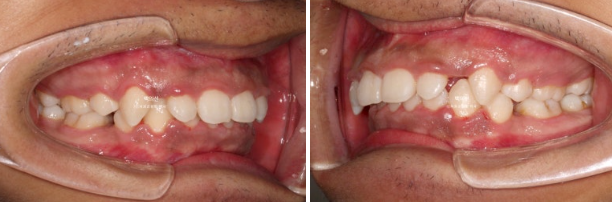

앞니 각도와 어금니 교합은 좋고 1급 교합관계를 보입니다.

중심선은 잘 맞으며 과개교합은 좋아졌습니다.

앞니가 상당히 뒤로 들어갔음에도 치료 전과 후 입매 변화가 크지는 않습니다.

인중 부위의 볼롬함 감소와 아랫입술의 후퇴 정도만 눈에 띕니다.

위 앞니 기준 뒤로 4-5mm 들어갔고 위로는 2-3mm 함입되었습니다.